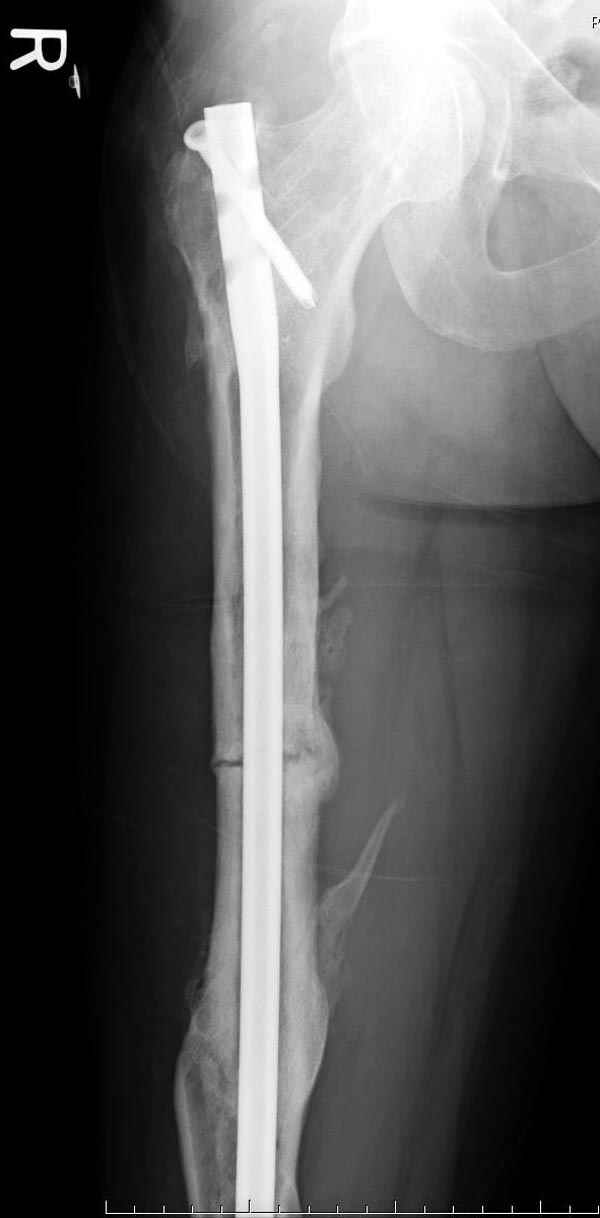

Представляю снимки больного с политравмой: леченного в другом мед.учреждении по поводу открытого перелома бедра, сперва аппаратом наружной фиксации, затем пластиной. Обратился к нам через 8 месяцев после удаления пластины с проблемой несросщего перелома бедренной кости, без клинических проявлении к инфицированию (не все снимки сохранены)

Рутинный интрамедуллярный остеосинтез с расверливанием и с фиксацией реконструктивным трокантерик штифтом (рис №1, №2),

если первые 4 месяца послеоперационного периода проходил без проблем, но на 5 месяце появились боли в дистальном отделе бедра и температура, т.е. симптомы медуллярного инфицирования (рис №3, №4).